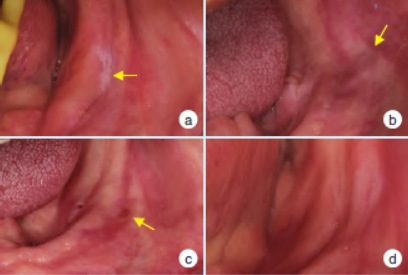

哥特式弓描记图像变化:若下颌运动轨迹从圆顶型、偏侧型或多顶点型转变为尖顶型,说明关节、神经和肌肉都逐渐稳定(图5)。口内黏膜变化:经治疗后,口内的黏膜逐渐由红肿、溃疡的状态,转变为健康的状态(图6)。

图5 治疗前后哥特式弓描记变化

图6 治疗前后口内黏膜变化